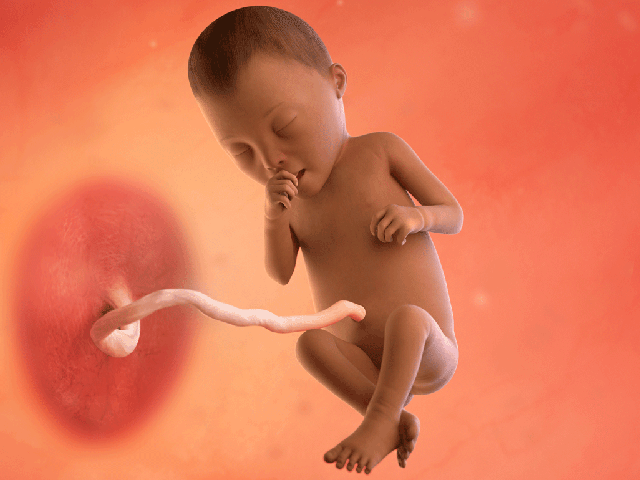

Bé yêu

– Bé yêu là một thai nhi, dài khoảng 34-35cm (tính từ đầu đến gót chân, như trái dừa), nặng 700-800g, với tim đập mạnh (120-160 lần/phút).

– Mí mắt bé bắt đầu mở, cho phép phản ứng với ánh sáng. Phản xạ nắm tay và mút ngón tay phát triển. Phổi tiếp tục hình thành phế nang, và lớp mỡ dưới da dày hơn, giúp bé tròn trịa.

– Siêu âm cho thấy bé cử động rõ nét (đá, xoay, nấc cụt), với lông mày, móng tay, và da hồng hào hơn. Thật tuyệt vời!